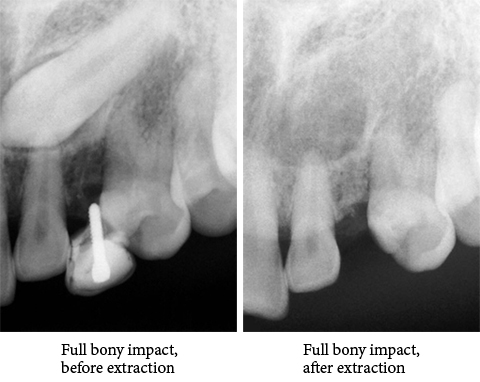

Orthodontic Treatment X-ray - Before

After Series of Teeth Extractions, Upper Left Canine Unerupted.

Ready to Start Ortho Treatment

Orthodontic Treatment X-ray - After